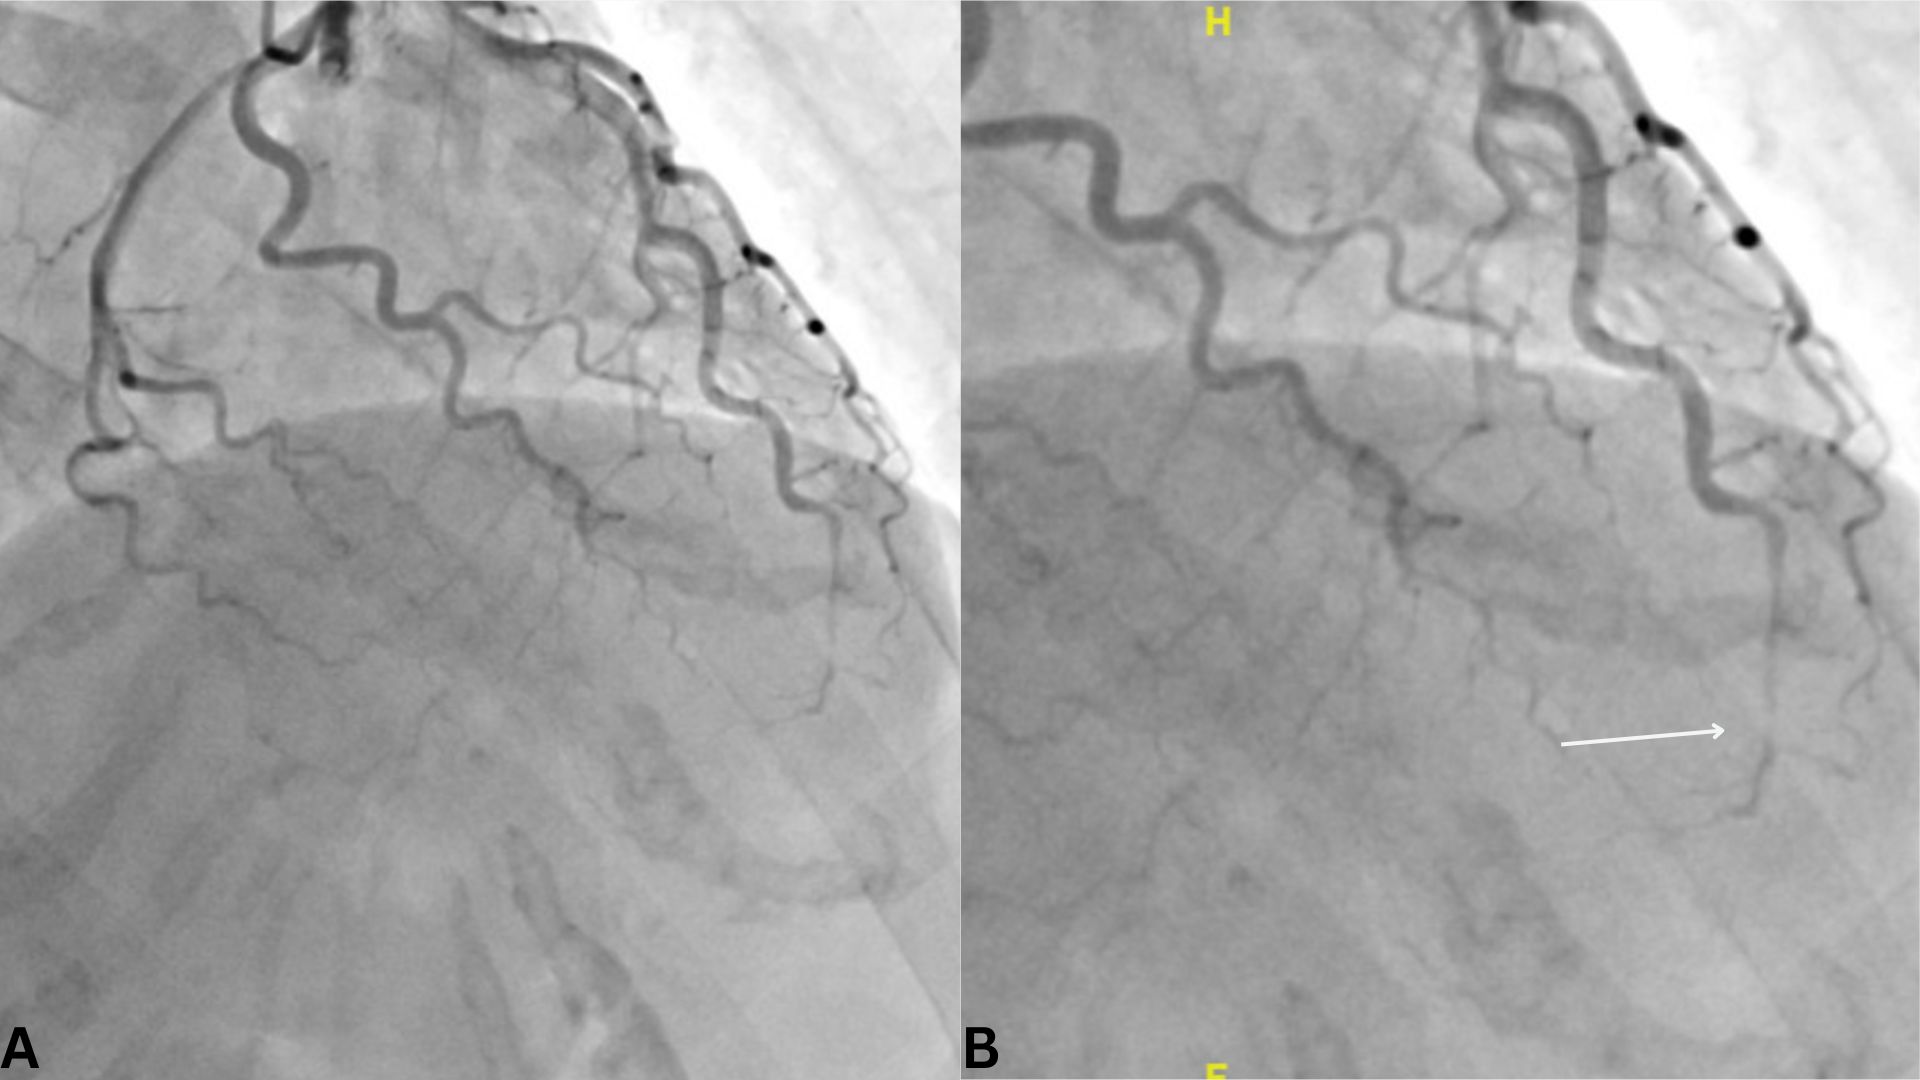

Case Presentation: A 56-year-old post-menopausal female with no prior medical history presented to the ED with two days of substernal chest pain radiating to the left shoulder, worsened 1-2 hours prior, and associated with fatigue. Two days earlier, she experienced significant emotional stress during a custody-related phone call, during which her husband observed her becoming flushed and trembling. Her usual systolic BP was < 110 mmHg, but she recorded 135 mmHg after the event. She denied systemic symptoms, smoking, or alcohol use. Family history included a grandfather with myocardial infarction at 77.In the ED, BP was 160/106 mmHg, and high-sensitivity troponin was elevated at 255 ng/L (normal: < 19 ng/L). ECG showed ST-segment elevation in leads II, III, aVF, V3, and V4, with ST depression and T-wave inversion in lead aVL. Coronary angiography revealed SCAD of the distal LAD with TIMI-2 flow and no CAD (Figure 1). Echocardiogram showed LVEF of 40-45% with apical hypokinesis and aneurysm. She was treated with DAPT, losartan, metoprolol, and atorvastatin, with symptom improvement and LVEF recovery to 52% on follow-up.